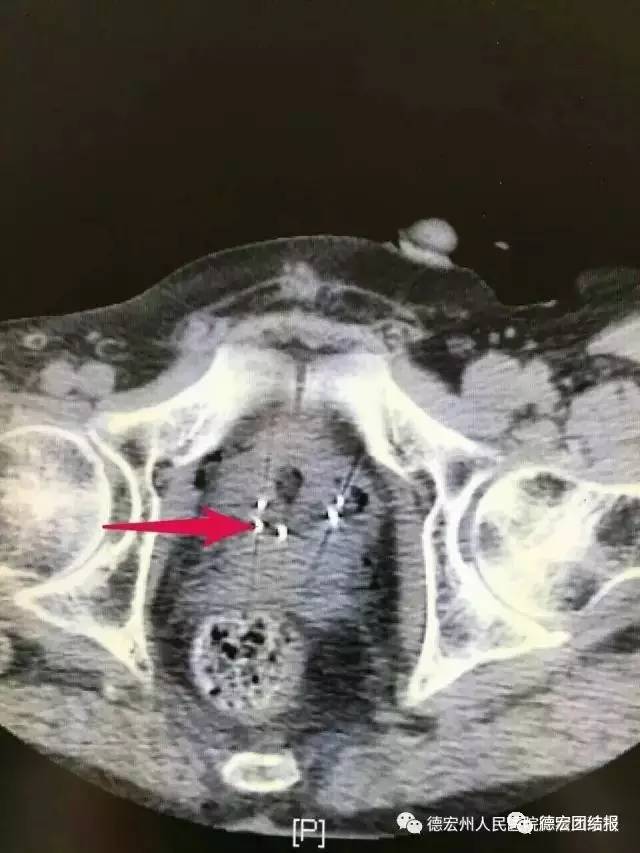

患者二,男,69岁,因确诊前列腺癌一年入院。确诊时分期晚,高龄,基础疾病较多(高血压、脑梗塞等),无手术指征。给予内分泌及药物去势治疗。患者近一月来出现排尿困难,再次到医院就诊。并于8月21日在院外专家的指导下接受了CT引导下经皮穿刺前列腺癌粒子植入治疗术。该手术的开展,标志着州人民医院前列腺癌的治疗翻开了新的篇章。

①手术中

② 术后粒子分布良好